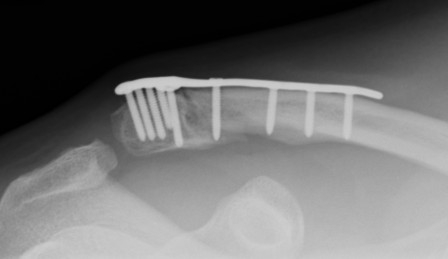

Dorsal locking plate +/- CC ligament reconstruction

Hook plate

Dorsal locking plate +/- CCL reconstruction

Disadvantage

Lateral screws under significant tension and subsequently higher rate of screw/plate pull-out

Sufficient lateral bone to obtain fixation

Consider having hook plate available / supplement with coraco-clavicular fixation

Dorsal locking plate with cerclage fibretape

- precontoured distal locking plate in 35 patients

- all united at mean of 4 months

- excellent outcomes scores

Xu et al BMC Musculoskeletal Disorders 2019

- 16 patients with locking plate versus 18 with plate + CC suture anchors

- shorter union time (14 v 16 weeks) and better outcomes (94 v 90 Constant) with suture anchors